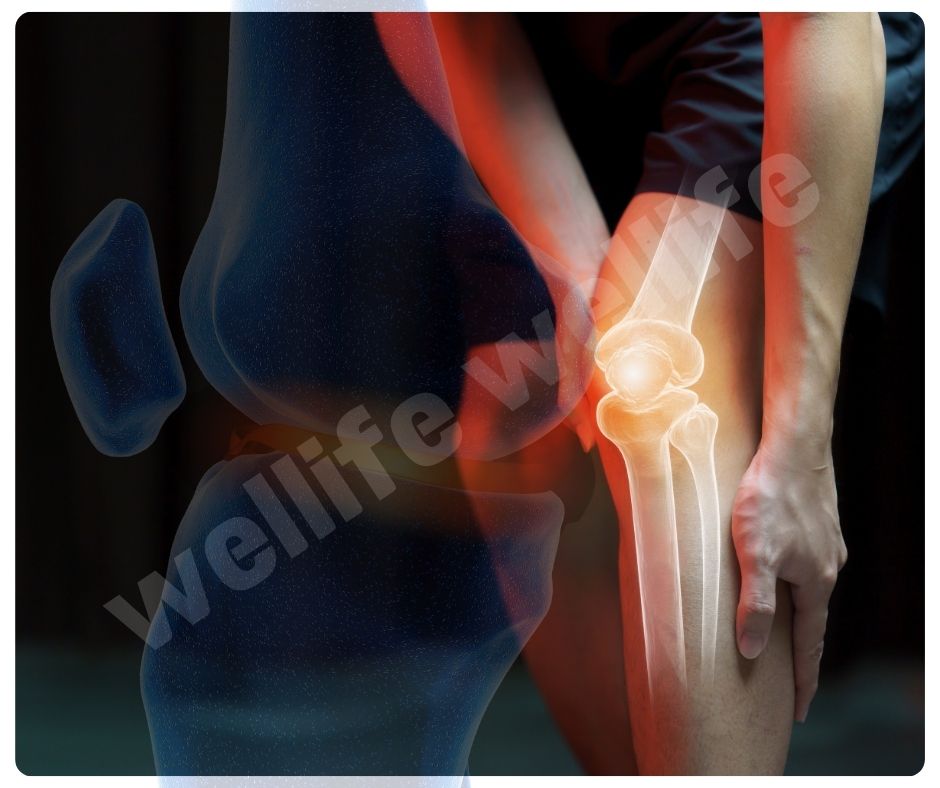

콘드로이친 효능은 관절의 움직임을 부드럽게 하고, 전반적인 관절 기능을 개선하는 데도 효과적입니다. 이는 관절염 환자뿐만 아니라 관절 건강을 유지하고 싶은 모든 사람들에게 유익합니다.

- 관절 윤활: 관절액의 생산을 촉진해 관절의 윤활을 개선하는 효능이 있습니다.

- 관절 유연성 향상: 관절의 유연성을 높여 활동성을 증가시킵니다.